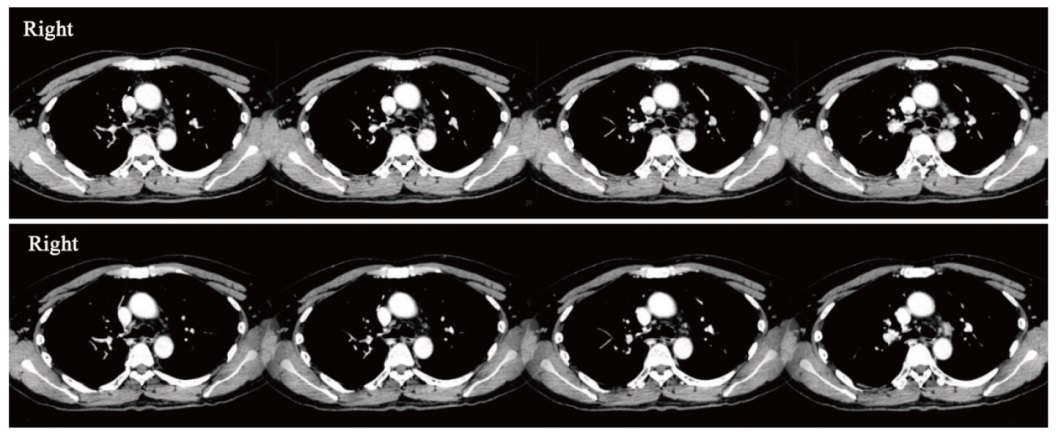

背景与目的:鞘内化疗是治疗实体瘤脑膜转移(leptomeningeal metastases,LM)的主要方法之一。既往的Ⅰ期临床研究证实了鞘内程序性死亡蛋白-1(programmed death-1,PD-1)抑制剂治疗黑色素瘤LM的安全性和潜在疗效。系统化疗联合PD-1抑制剂的协同抗肿瘤作用已被广泛认可。本研究旨在探索鞘内注射培美曲塞联合PD-1抑制剂治疗实体瘤LM的安全性及可行性。 方法:以广州医科大学附属惠州医院/惠州市第三人民医院收治的实体瘤LM患者为研究对象,采用“3+3”剂量递减策略,寻找推荐的安全给药剂量。培美曲塞给药方案为初始诱导治疗2次/周,连续2周;随后巩固治疗1次/周,连续4周;治疗有效的患者给予每个月1次维持治疗。PD-1抑制剂给药从第4次培美曲塞给药开始,每2周1次,连续6周;随后对治疗有效的患者,与培美曲塞同时给予每个月1次维持治疗。单次给药起始剂量为PD-1抑制剂(特瑞普利单抗)40 mg、培美曲塞15 mg。主要研究终点为安全性及推荐给药剂量,安全性基于不良反应进行评估。同时观察临床有效率(clinical response rate,CRR)、疾病控制率(disease control rate,DCR)和总生存期(overall survival,OS)。本研究经广州医科大学附属惠州医院/惠州市第三人民医院伦理委员会审批通过(伦理编号:2024-KY-029-01)。 结果:2024年6—9月共入组7例患者(男性3例,女性4例,中位年龄57岁),包括非小细胞肺癌6例和乳腺癌1例。所有患者的脑脊液(cerebrospinal fluid,CSF)细胞学检查结果均为阳性。6例存在LM相关神经功能障碍。5例存在LM相关影像学异常。6例完成诱导及巩固治疗并接受维持治疗。1例因细菌性脑膜炎未完成巩固期最后1次PD-1抑制剂鞘内给药,感染控制后接受维持治疗。总不良反应发生率为100%(7/7),包括骨髓抑制7例(100.00%)、转氨酶升高3例(42.86%)、乏力2例(28.57%)和甲状腺功能减退1例(14.29%)。其中3级不良反应发生率为42.86%(3/7),全部为骨髓抑制。免疫相关不良反应(immune-related adverse event,irAE)发生率为14.29%(1/7),为Ⅱ级甲状腺功能减退。未见剂量限制毒性(dose-limiting toxicity,DLT)发生,推荐剂量为PD-1抑制剂40 mg联合培美曲塞15 mg。3例患者神经功能改善,1例CSF细胞学检查结果转阴,2例影像学缓解。根据神经肿瘤疗效评估(response assessment in neuro-oncology,RANO)标准,CRR为57.14%(4/7),DCR为100%(7/7)。3例出现远隔效应,分别表现为脑转移灶、原发肺病灶及纵隔淋巴结缩退。截至2025年4月10日,1例死亡,中位随访时间为7.7(5.9~9.3)个月。中位OS未达到。6个月OS率为85.71%。 结论:鞘内注射培美曲塞联合PD-1抑制剂治疗非小细胞肺癌等实体瘤LM患者显示出良好的安全性和可行性,并且具有潜在的临床疗效。

Background and purpose: Intrathecal chemotherapy is one of the mainstay treatment options for leptomeningeal metastases (LM) from solid tumors. A previous phase Ⅰ study demonstrated the safety and potential efficacy of intrathecal anti-programmed death receptor 1 (anti-PD-1) for LM from melanoma. The synergistic efficacy of systemic chemotherapy combined with anti-PD-1 has been widely known. This study aimed to evaluate the safety and feasibility of intrathecal chemotherapy (pemetrexed) and anti-PD-1 (toripalimab) for LM patients from solid tumors. Methods: The subjects were patients with LM from solid tumors who were treated at Affiliated Huizhou Hospital of Guangzhou Medical University/Third People’s Hospital of Huizhou City. A 3+3 dose de-escalation strategy was implemented to determine the recommended dose with an initial dose of PD-1 inhibitor (toripalimab) 40 mg and pemetrexed 15 mg. Pemetrexed was administered twice weekly for the initial 2 weeks of induction therapy, once weekly for the subsequent 4 weeks of consolidation therapy, and once monthly during maintenance therapy. PD-1 inhibitor was initiated at the 4th administration of pemetrexed, administered every 2 weeks for 6 weeks; subsequently, responders continued monthly maintenance therapy alongside pemetrexed. The primary objective was to assess safety based on adverse events and the recommended dose. All participants were observed to investigate the clinical response rate (CRR), disease control rate (DCR) and overall survival (OS). This study was approved by the ethics committee of Affiliated Huizhou Hospital of Guangzhou Medical University/Third People’s Hospital of Huizhou City (ethics number: 2024-KY-029-01). Results: Seven patients (male: 3, female: 4, median age: 57 years) were enrolled between June and September 2024, including non-small cell lung cancer (6) and breast cancer (1). All patients presented with positive cerebrospinal fluid (CSF) cytology. Six patients presented LM-related neurological dysfunction. Five patients showed LM-related neuroimaging findings. Six patients completed the induction and consolidation therapy, and subsequently received maintenance therapy. One patient, due to bacterial meningitis, did not complete the final administration of toripalimab during consolidation therapy, and maintenance therapy was administered after infection control. Adverse events rate was 100% (7/7), including myelosuppression (100.00%, n=7), elevation of hepatic aminotransferases (42.86%, n=3), fatigue (28.57%, n=2) and hypothyroidism (14.29%, n=1). Three (42.86%) patients had grade 3 adverse events (myelosuppression). The immune-related adverse event (irAE) rate was 14.29%, manifested as hypothyroidism (Grade 2). No dose-limiting toxicity (DLT) was observed. Thus, no de-escalation was applied. The recommended dose was determined to be PD-1 inhibitor 40 mg in combination with pemetrexed 15 mg. Three patients showed improved neurological dysfunction, 1 with CSF cytological response, and 2 with neuroimaging improvement. CRR was 57.14% (4/7) by response assessment in neuro-oncology (RANO) proposal criteria. DCR was 100% (7/7). Three patients exhibited abscopal effects with regression of brain metastasis lesions, primary lung lesion and mediastinal lymph nodes, respectively. As of April 10, 2025, 1 patient died. The median follow-up time was 7.7 (5.9-9.3) months. The median OS was not reached with a 6-month OS rate of 85.71%. Conclusion: The combination therapy of intrathecal pemetrexed and a PD-1 inhibitor was well-tolerated and feasible, while also exhibiting potential clinical efficacy in treating LM from solid tumors including non-small cell lung cancer.